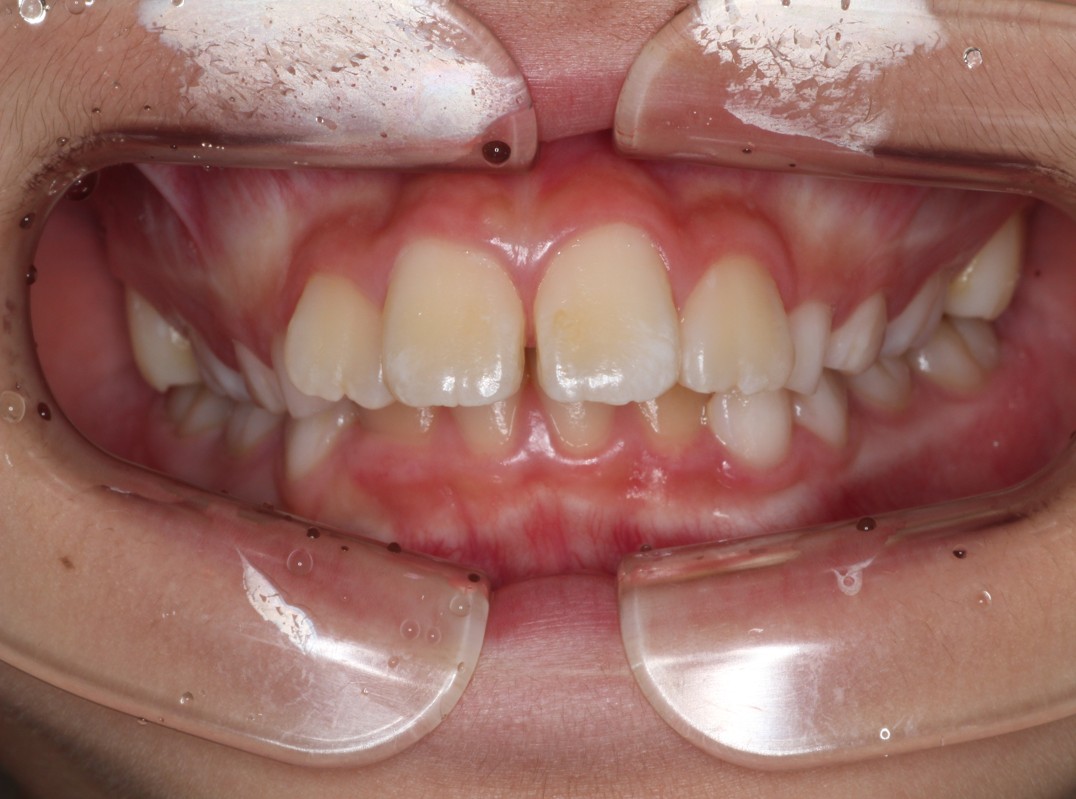

治療前

出っ歯を治したい。永久歯が生えず不安に思っている。 |

出っ歯と下の永久歯が生えるスペースがないことを主訴にご来院されました。 |